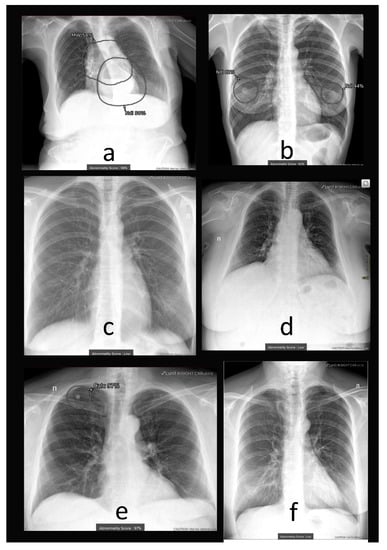

2.1. AI System

4.1. Additional Data and Technical Assessment of the Quality of Input CXR

4.2. Comprehensive Assessment of Identified Radiographic Features